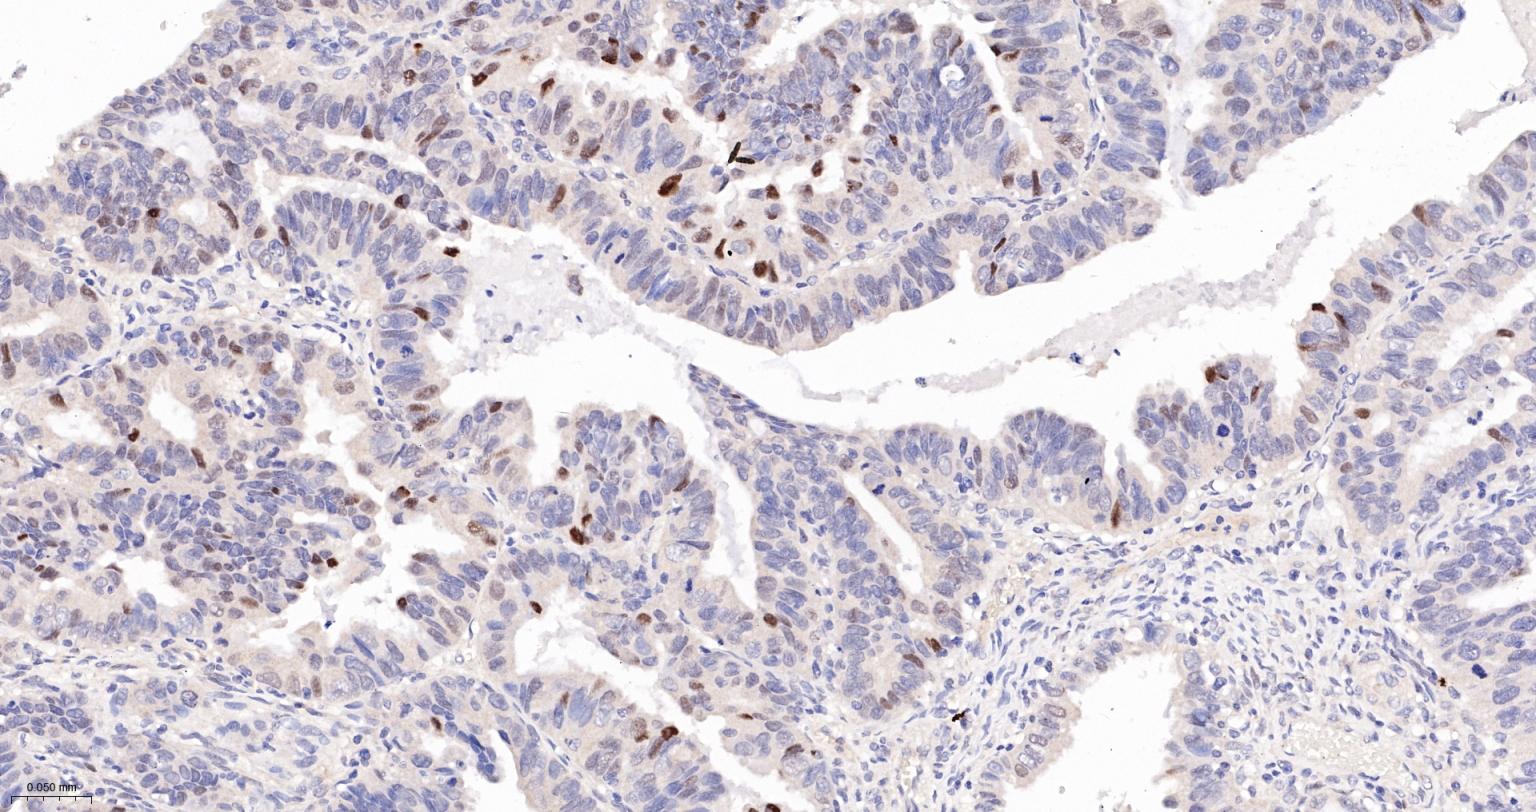

Paraformaldehyde-fixed, paraffin embedded Human Ovarian Cancer; Antigen retrieval by boiling in sodium citrate buffer (pH6.0) for 15 min; The section was incubated with P53 Monoclonal Antibody, Unconjugated (bsm-33058M) at 1:600 overnight at 4°C, followed by conjugation to the bs-40296G-HRP and DAB (C-0010) staining.